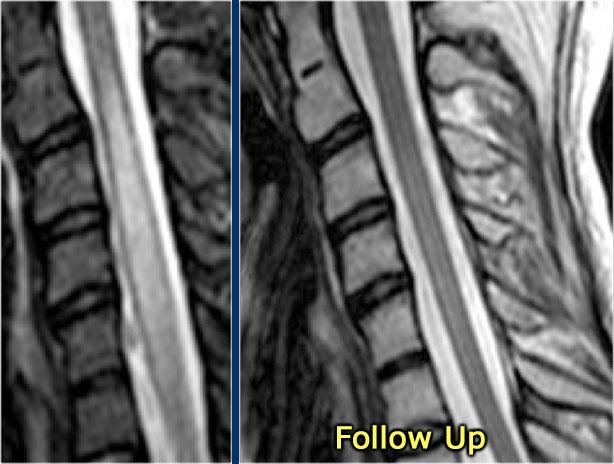

Đây là hình ảnh của một trường hợp điển hình.

Nhiều khi tiền sử lâm sàng rất hữu ích như trong trường hợp này.

Bệnh nhân nữ 24 tuổi có rối loạn thị giác một mắt, sau đó vài năm xuất hiện yếu và rối loạn cảm giác ở chi dưới và chi trên.

Hiện tại bệnh nhân đến khám vì rối loạn cảm giác ở cả hai chi dưới.

Vì vậy chúng ta đã nghĩ đến MS.

Trong tủy sống có một số tổn thương bờ rõ, nhưng cũng có một số tổn thương bờ không rõ, mờ nhạt.

Hình ảnh cắt ngang cho thấy vị trí ở phía lưng và hình dạng tam giác điển hình.

Tiếp tục xem các hình ảnh sau tiêm thuốc tương phản từ

Trên các hình ảnh sau tiêm thuốc tương phản từ, không thấy ngấm thuốc.

Các tổn thương MS hoạt động ở tủy sống có thể ngấm thuốc, nhưng không phổ biến như các tổn thương hoạt động ở não.

Khi phát hiện tổn thương ở tủy sống, việc chụp thêm não cũng rất hữu ích.

Đôi khi bệnh nhân chỉ được chỉ định chụp MRI cột sống và không có đủ thời gian để thực hiện toàn bộ khảo sát não.

Trong những trường hợp đó, hãy cân nhắc chỉ thực hiện chuỗi xung FLAIR mặt phẳng đứng dọc.

Tiếp tục xem các hình ảnh của não.

MRI não cho thấy các tổn thương quanh não thất và một tổn thương ở thể chai.

Các vị trí này rất đặc trưng cho MS.